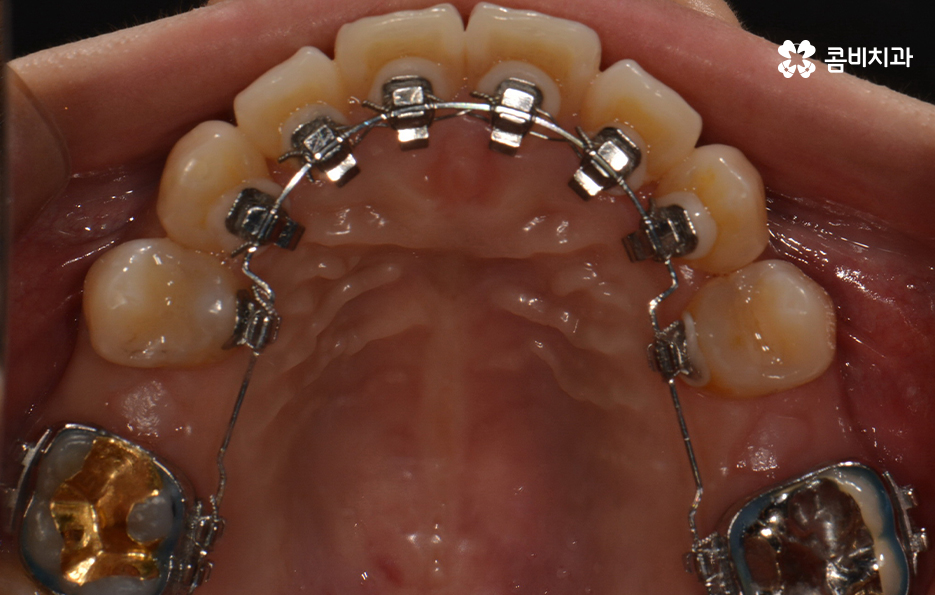

윗니가 설측으로 시술이 진행되고 있는 모습이며

발치를 한 부위 안쪽으로 치아가 이동하기 때문에

돌출입의 개선이 함께 이뤄지며 치열뿐 아니라

얼굴과 자연스럽게 어울리는 결과를 얻을 수 있습니다.

교정 치료 진행과정의 경과 모습

초기에 시술이 진행된 모습에 비해서 윗니가 가지런해졌고

돌출되었던 치아가 안쪽으로 많이 들어온 모습입니다.

발치를 했던 부위가 어딘지 잘 모를 정도로

윗니가 안쪽으로 들어와서 가지런하게

치열이 자리 잡고 있는 모습입니다.